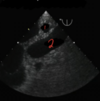

2

3

4

5

Perfectly

6